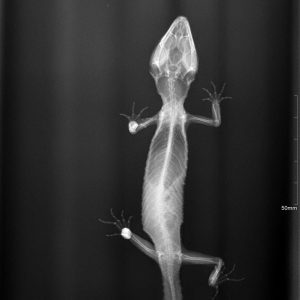

El diagnóstico por imagen es una herramienta fundamental en la medicina veterinaria moderna, ya que permite evaluar de forma precisa y no invasiva las estructuras internas del paciente. A través de técnicas avanzadas como la radiografía digital y la ecografía, es posible identificar alteraciones anatómicas y funcionales que facilitan un diagnóstico temprano y un manejo clínico más eficaz.

Nuestro servicio en Mastervet está orientado a ofrecer estudios de alta calidad, con equipos actualizados y protocolos adaptados a cada caso. Realizamos evaluaciones completas que incluyen la interpretación detallada de las imágenes y la emisión de informes clínicos claros, contribuyendo a la toma de decisiones terapéuticas.

Trabajamos en estrecha colaboración con veterinarios clínicos para asegurar una correcta correlación entre los hallazgos de imagen y la situación clínica del paciente, optimizando así el abordaje diagnóstico y el seguimiento evolutivo.